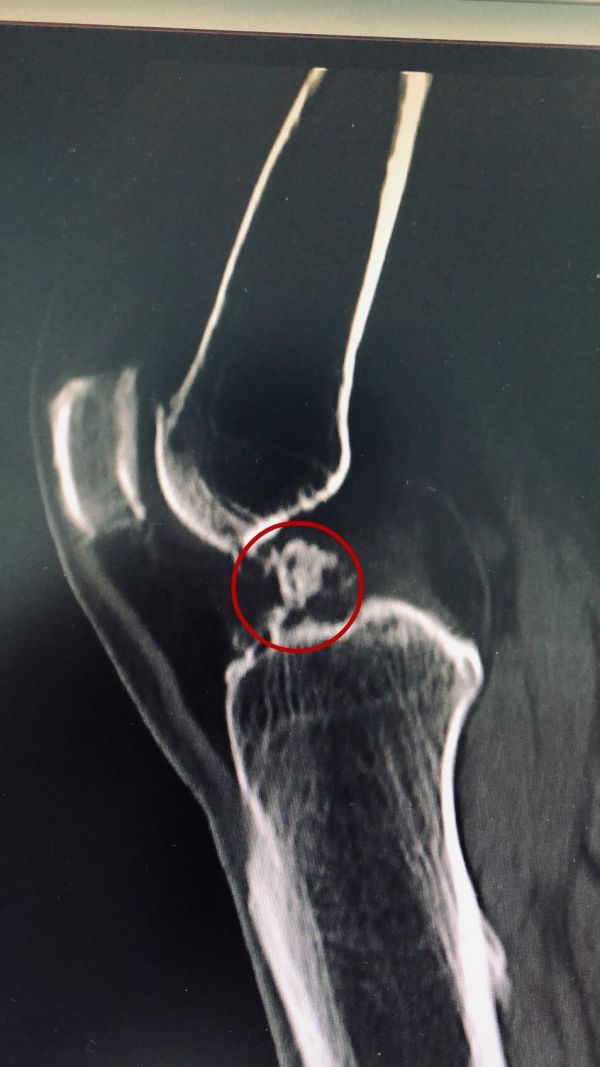

经过一段时间的住院治疗,王女士膝关节疼痛得到缓解,但由于“小石子”仍紧紧卡压在股骨髁间窝,根本问题并没有解决。针对王女士的情况,骨伤二科医师团队经过反复研究评估,制定周密的手术康复计划,决定在局麻状态下为王女士进行手术治疗,取出游离体。

骨伤二科主治医师覃剑、梅凌为王女士详细讲解手术过程,消除患者的心理恐惧。一周前,王女士接受了局麻微创关节镜手术治疗,医生通过几个小孔,从患者膝关节腔取出2个蚕豆大小游离体。术后,患者迅速恢复,5月25日康复出院。